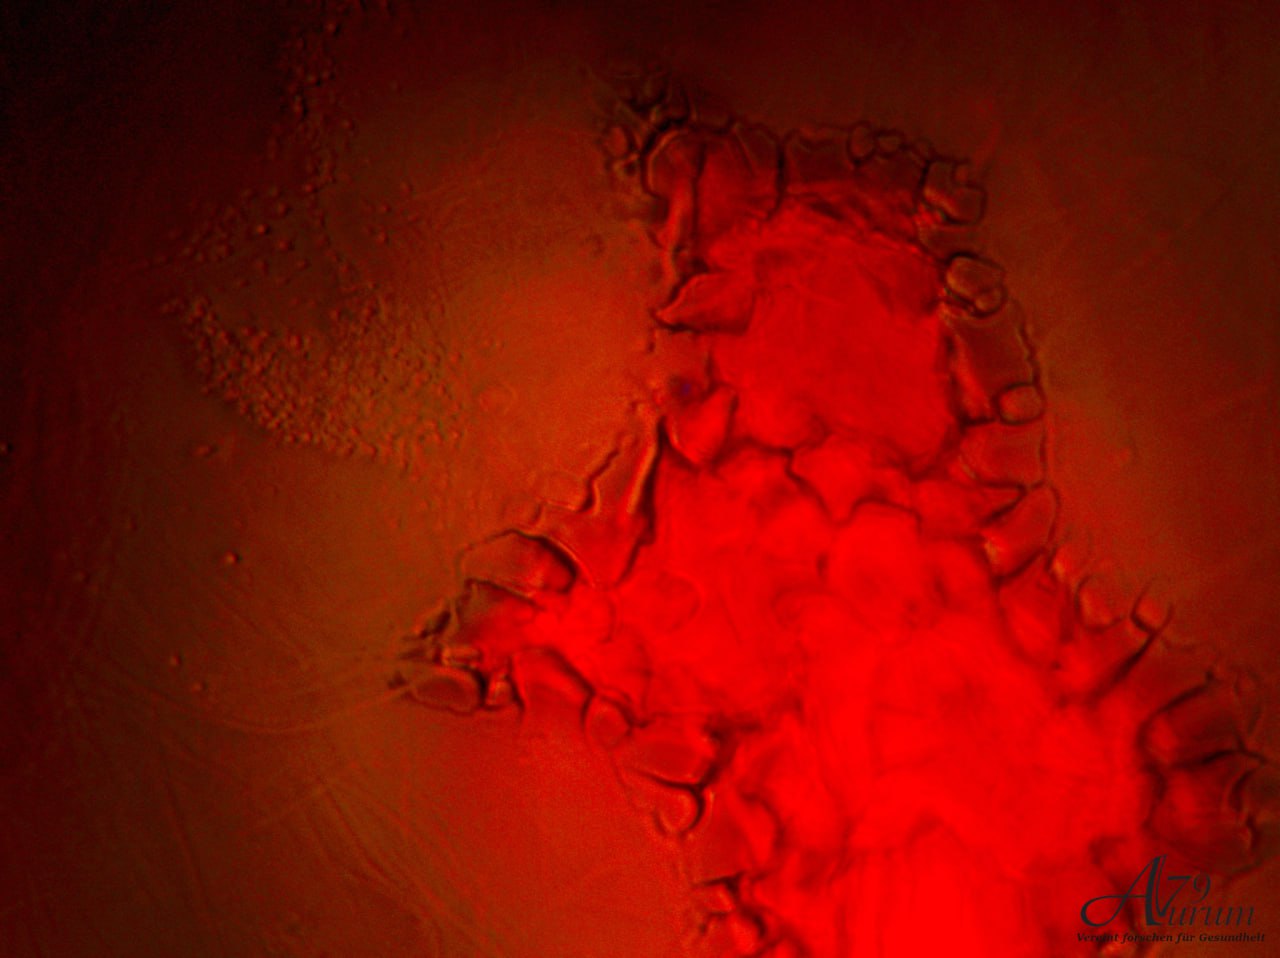

Vitalblutanalyse 1. Tag

Dichtem Vorkommen von kreisförmigen Zellen. Leichte Aggregationen sichtbar, aber keine eindeutigen abnormalen Formen oder Parasiten erkennbar. Weitfeld-Okulare mit 10-facher Vergrößerung & 10x Objektiv

Zeigt zahlreiche kreisförmige Strukturen (Erythrozyten) mit variierender Intensität. Einige Zellen scheinen aggregiert, andere einzeln verteilt. Weitfeld-Okulare mit 10-facher Vergrößerung & 40x Objektiv